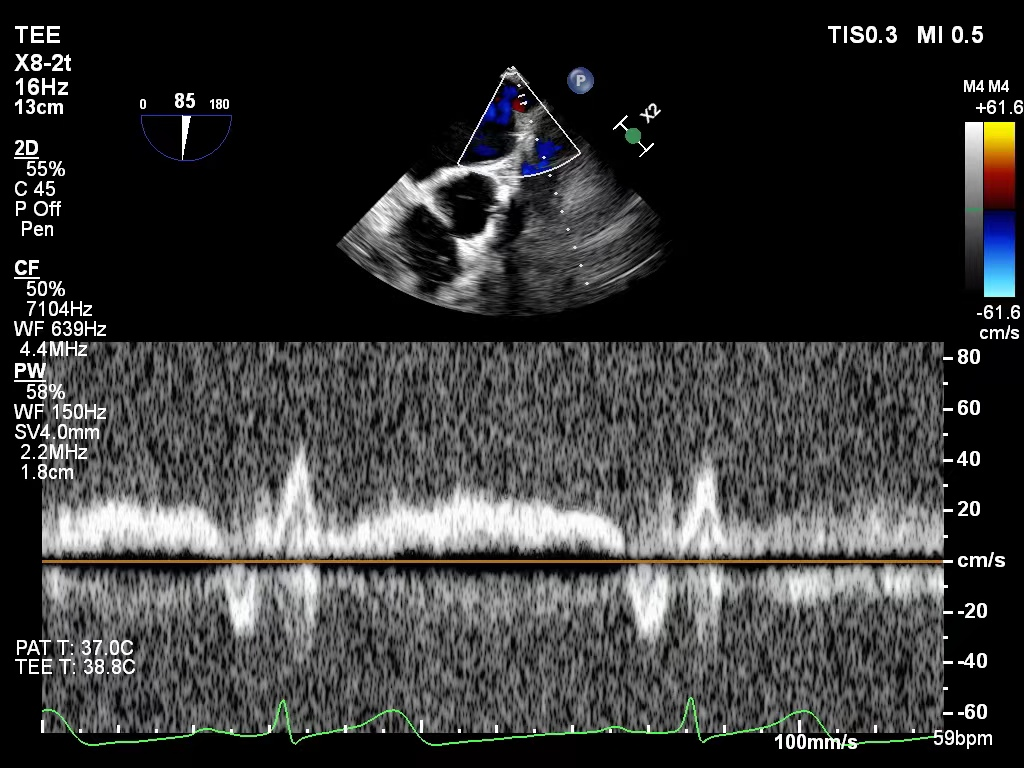

X-plane视图下对准反流束中心进入左室

图片

肺静脉血流频谱恢复正向